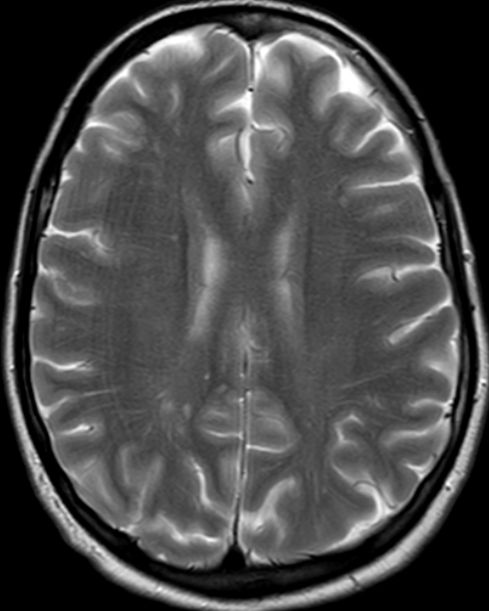

53-jähriger Mann mit Adenokarzinom des rechten

Lungenoberlappens T1 N3 M1bra.![]() |

![]() |